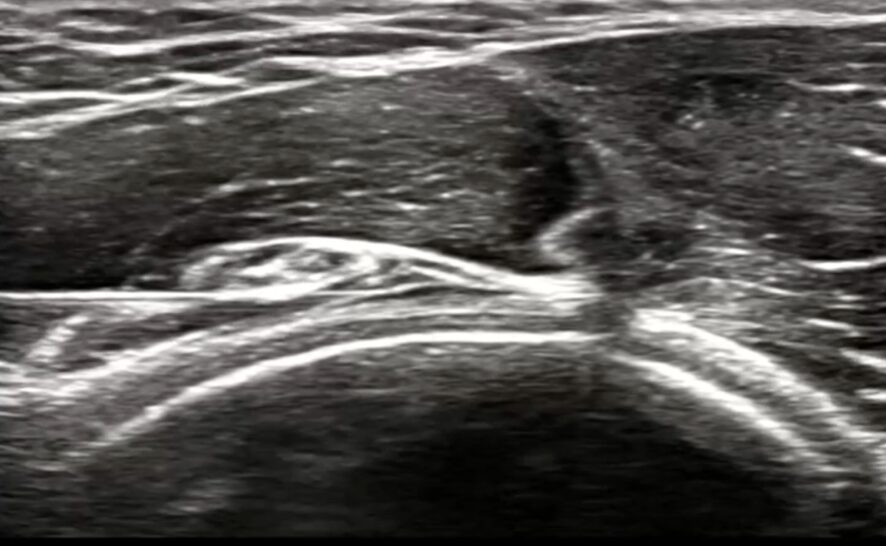

超音波(エコー)による“痛みの可視化”

ここが最も重要なステップです。超音波(エコー)検査装置を使い、痛みの原因となっている部位をリアルタイムの画像で観察します。エコーを用いることで、レントゲンやMRIでは捉えきれない筋膜の重なり、肥厚、神経の腫れや癒着を、患者様ご自身の目で確認することができます(1)。

診断によって癒着部位が特定されたら、いよいよ治療です。ハイドロリリースは、超音波(エコー)で身体の中をリアルタイムに見ながら行うことで、その安全性と効果を最大限に発揮します。

ハイドロリリースは、「ハイドロ(液体)」の力で、癒着した組織を「リリース(剥離・解放)」する治療法です。具体的には、エコーで神経や筋膜、血管の位置を正確に確認しながら、非常に細い注射針を進め、癒着している部位に生理食塩水や低濃度の麻酔薬を注入します。

注入された液体の水圧によって、これまで癒着していた組織の間にスペースが生まれ、物理的に剥がれていきます。これにより、神経や筋膜の滑走性が回復し、圧迫から解放されるのです。

エコーガイド下で行うことの最大の利点は、安全性です。神経や血管をリアルタイムで視認できるため、それらを誤って傷つけるリスクを最小限に抑えることができます。治療は外来で5〜10分程度で完了し、身体への負担も非常に少ないのが特徴です。